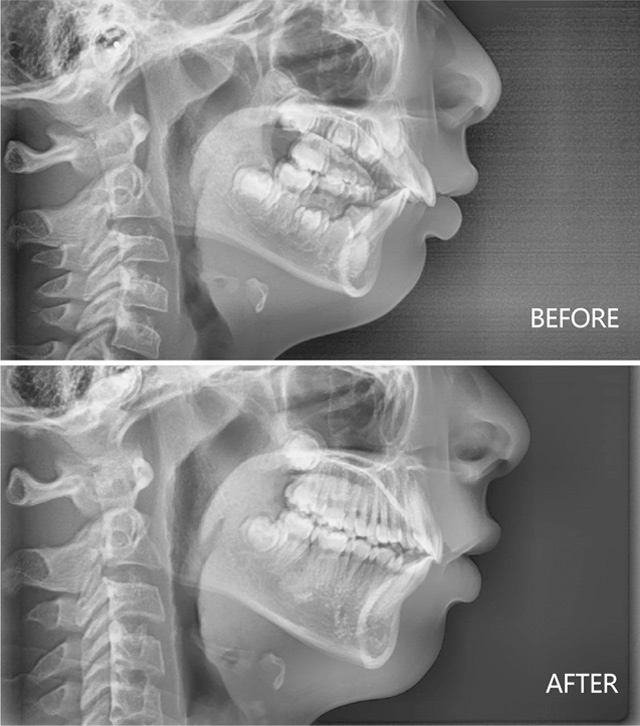

下巴后缩合并深覆盖治疗前后

9岁女孩下巴后缩治疗前后

8岁男孩下巴后缩治疗前后